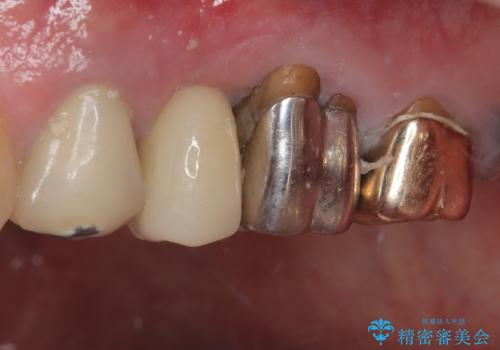

抜歯即時埋入後にはずっと気になっていた排膿が消え、痛みも腫れも特になく、3ヶ月という短期間で無事に治療を終えることができました。

破折した奥歯 抜歯即時埋入インプラントによる補綴治療